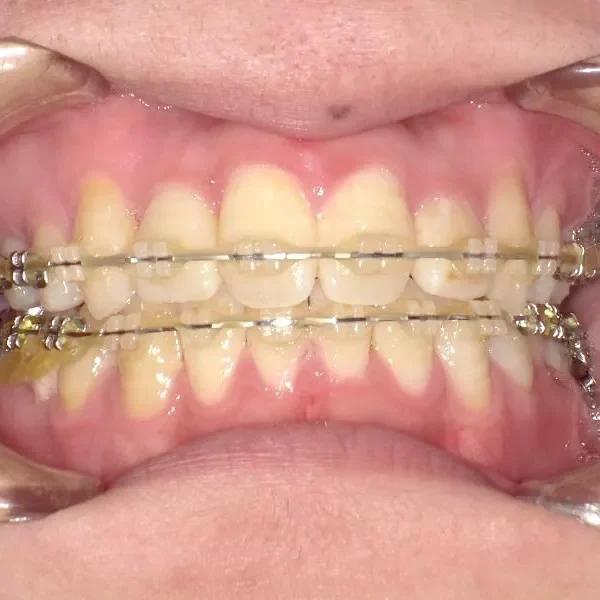

治療終了後

治療回数42回、3年1ヶ月の治療期間で矯正治療を終了しました。

主訴が改善され、ご満足頂きました。

正中のすき間については保定期間にも調整しています。